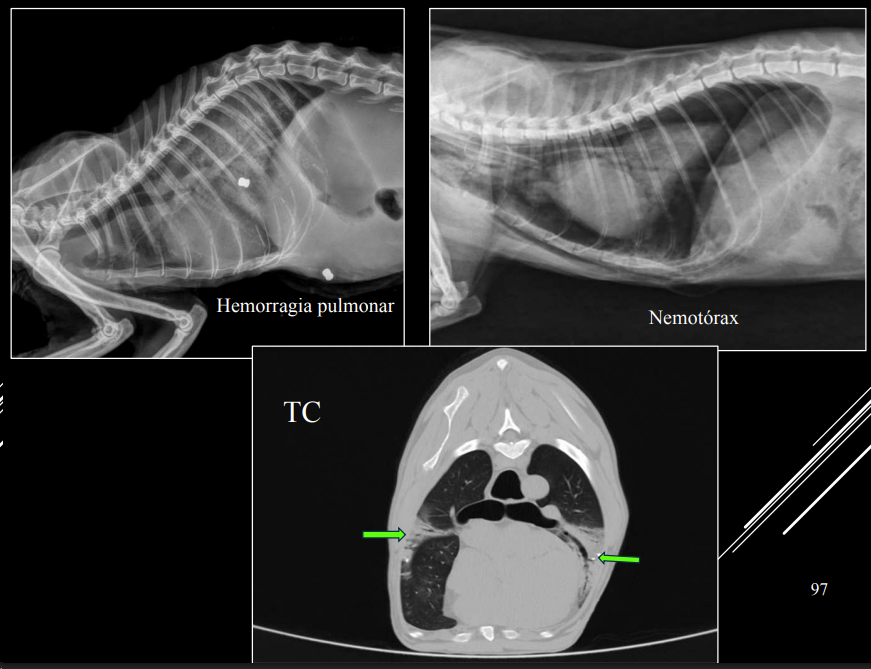

Neumotórax

Si hay un neumotorax y neuromediastino, el neumomediastino siempre es el causante

- Aire en cavidad pleural.

- RX:

- Desplazamiento dorsal del corazón (LL).

- Colapso pulmonar.

- Trama pulmonar no llega a pared torácica.

- Espacio radiolúcido entre pulmón y pared.

Cuando hay un neumotorax, al retraerse el pulmon se presentara un patron alveolar. Si el aire puede ir a ambos lados las presiones se compensan, anotensión. Si solo entra y no sale aumentara la presion y tendremos un neumotorax atensión